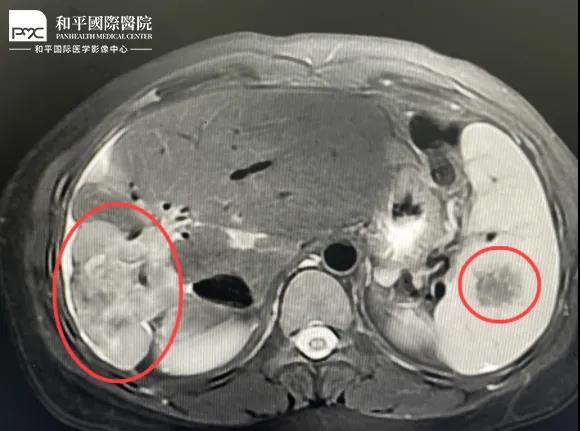

檢查結果對于這家人而言猶如晴天霹靂,經核磁共振等相關檢查,當地醫生懷疑是肝癌,建議手術治療。悲痛中,家人們對這樣的結果表示無法接受,想要多去幾家醫院看看,為了進一步確診,王小姐來到我院醫學影像中心進行檢查,事情竟發生了戲劇性反轉。

根據影片分析,結合王小姐有系統性紅斑狼瘡的病史,長期服用激素,免疫力低下,近期又有低熱盜汗的癥狀,影像中心執行主任侯文杰初步判斷王小姐是得了肝結核,并不是肝癌!

由于肝結核是臨床非常少見的病例,單靠影像診斷是很難診斷正確的,在侯主任的建議下,王小姐做了穿刺活檢,診斷結果的確是肝結核。